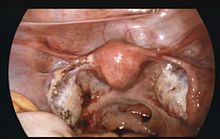

![]() | |

Laparoscopic view, looking down at the uterus (marked by blue arrows). In the left Fallopian tube there is an ectopic pregnancy and bleeding (marked by red arrows). The right tube is normal. | |